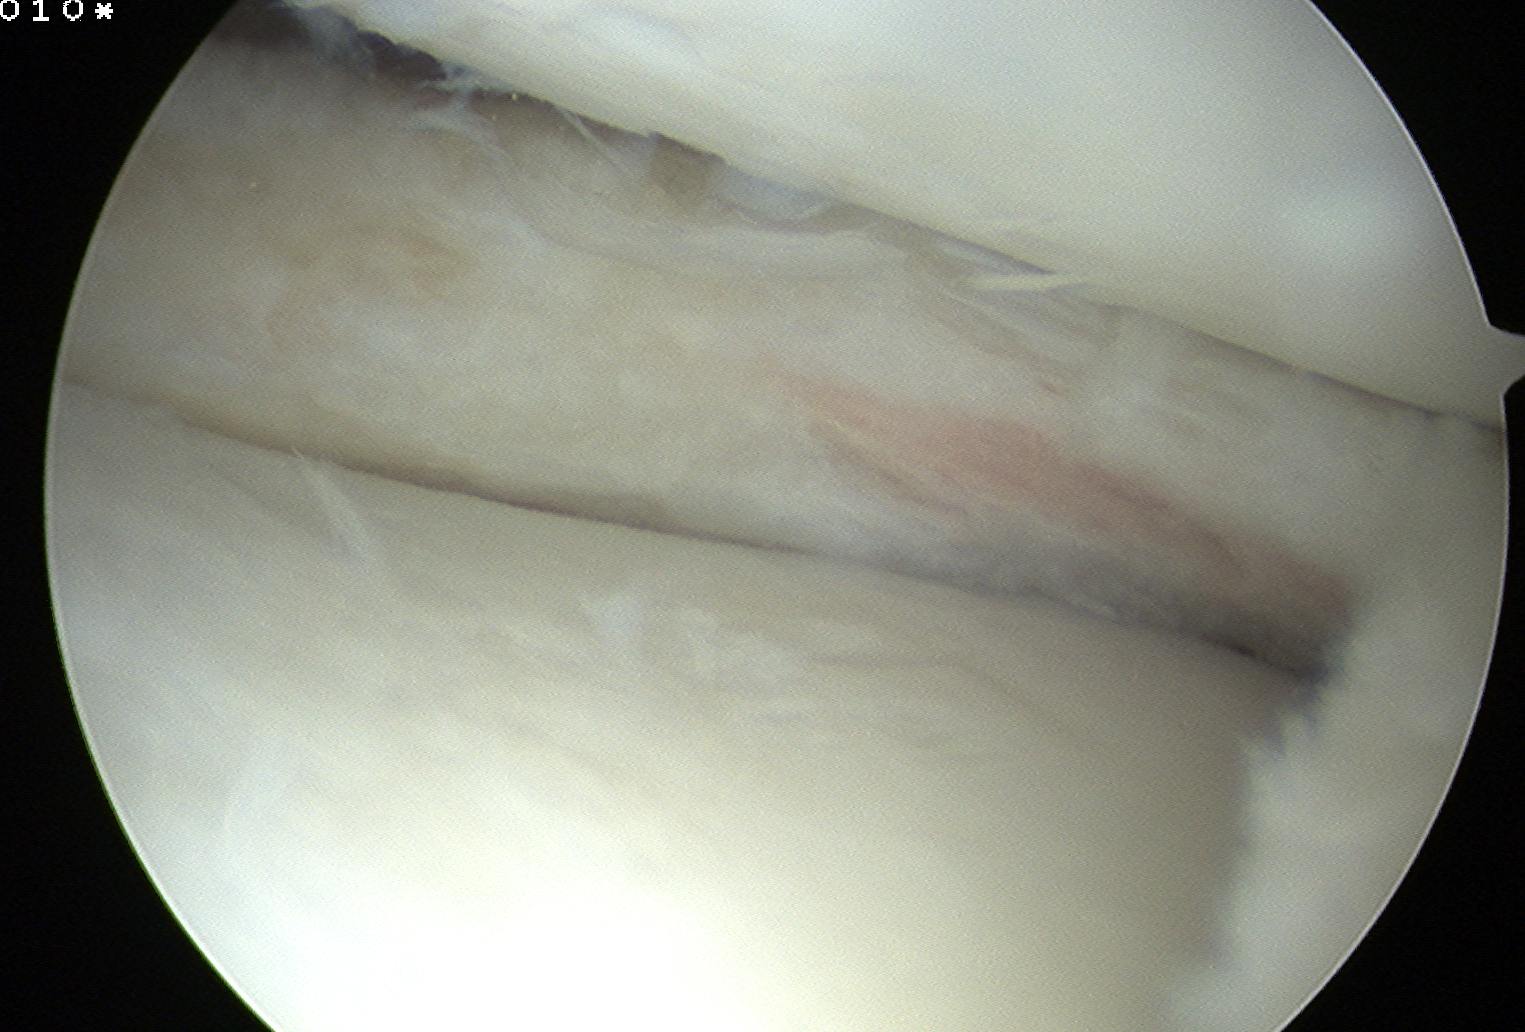

Technique Saucerisation

Issues

- demanding and technically difficult

- takes 1 - 2 hours

- difficult to know how much to resect

- need to ensure don't damage chondral surfaces

- reported cases of rapid and severe chondrolysis post resection in young patients

Technique

- make incision with scissors in medial aspect

- resect posterior part

- saucerise laterally and anteriorly

- need to ensure don't detach anterior horn